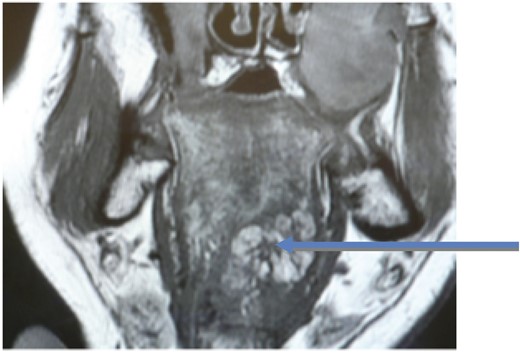

A 42-year-old male with Gorlin syndrome was referred by his General Practitioner to the Ear, Nose and Throat department with progressive dysphagia and voice change. Examination including fibre-optic nasendoscopy was normal, whilst magnetic resonance imaging (MRI) of the tongue base revealed no pathology. Following a period of observation, his symptoms progressed and a repeat MRI showed a discrete mass in the tongue base (Fig. 1). A panendoscopy was performed and biopsies demonstrated a myolipoma.

Coronal view MRI with arrow showing the myolipoma at the tongue base.